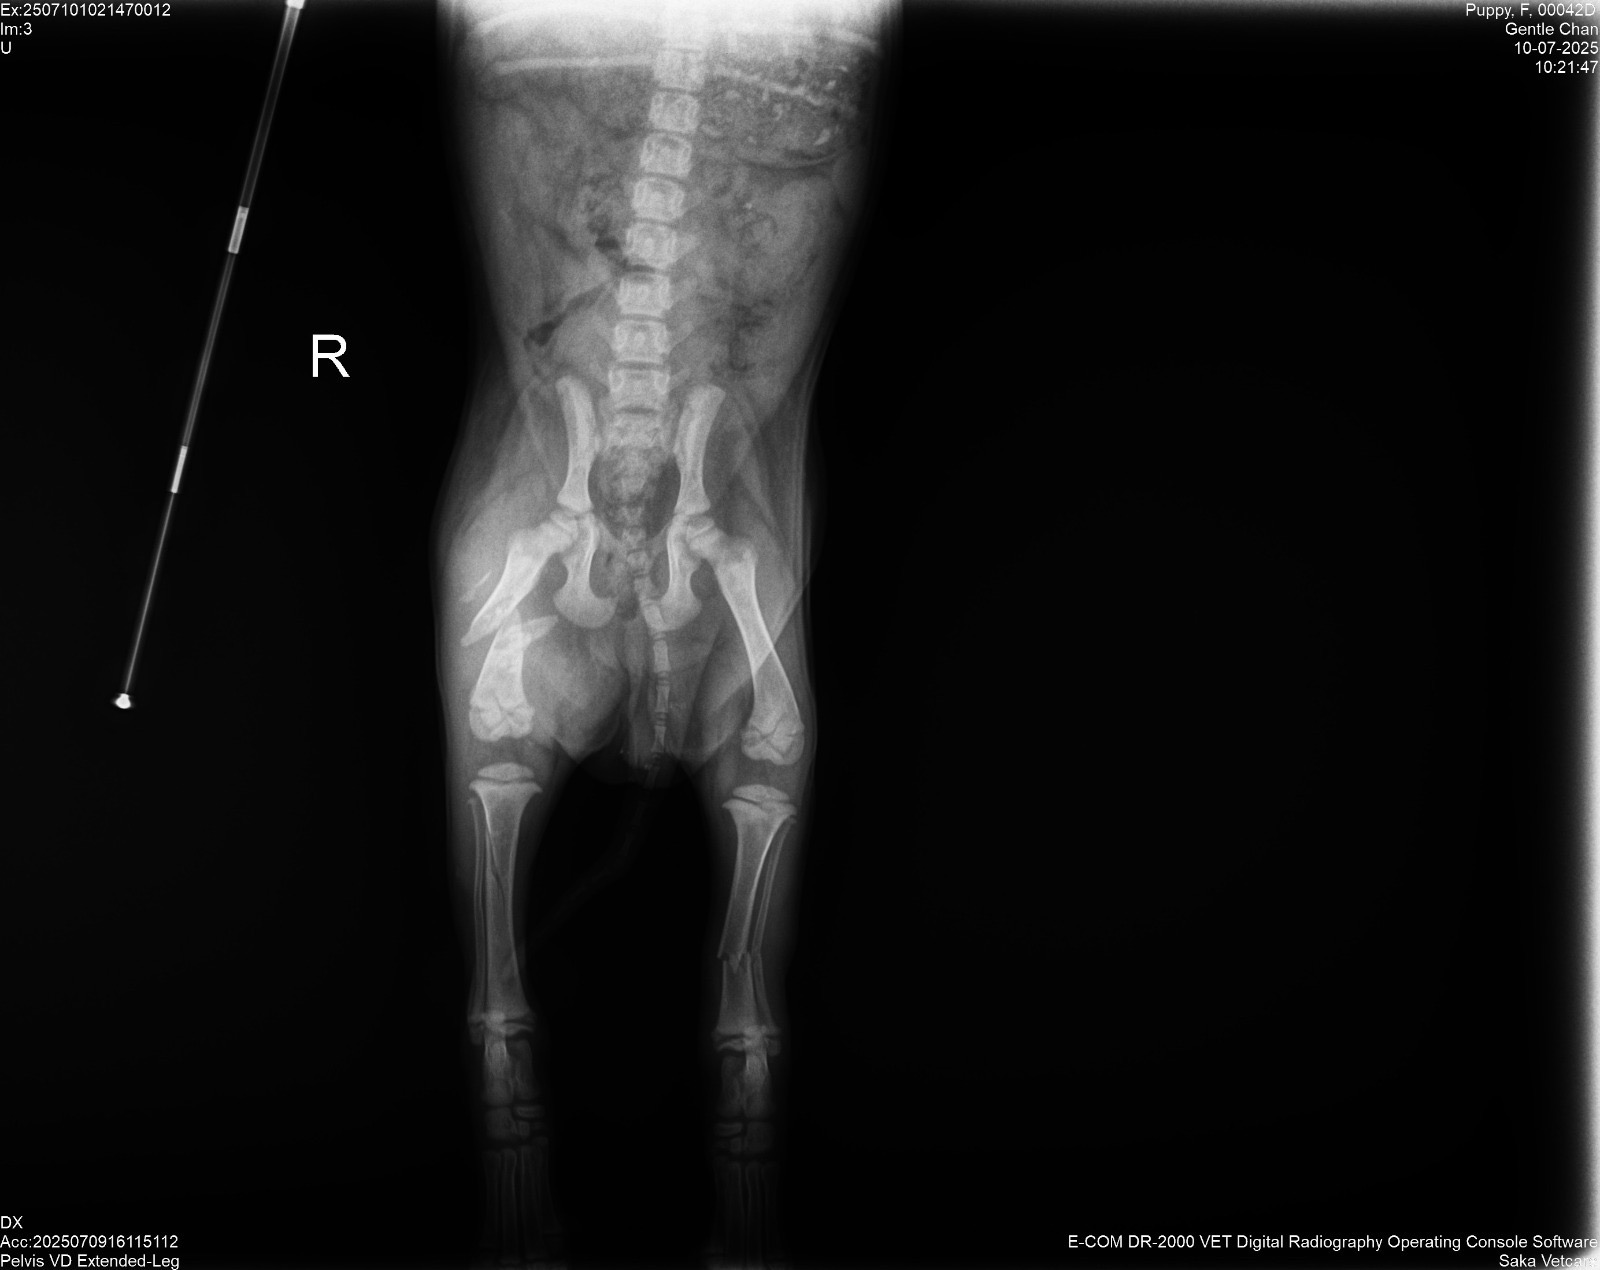

Kinta is a 6-week old purebred Kintamani puppy indigenous to Bali. I found her in poor shape outside of a hostel and brought her to a sanctuary that referred us to a clinic. After a consultation, some x-rays, casts, and medicine, we found that she had 3 breaks along her hind legs. With surgery, she has very good chances at making a full recovery. Without, she will likely be permanently disabled in both back legs.